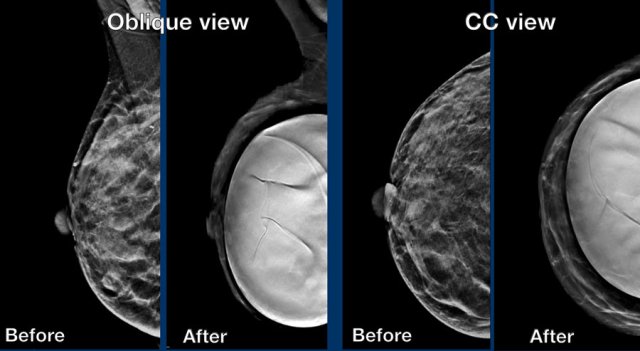

Mammography

Same patient before and after prepectoral breast augmentation.

Especially prepectoral implants can reduce mammographic assessment.

Still

mammography and 3D tomosynthesis can be well performed and in fact has the highest

PPV for recognition of extra capsular silicone.

It also objectively detects changes

in time, shows calcifications, can show surrounding fluid shadow and of course adds

important findings in fibroglandular tissue.

Eklund technique

Special views can be performed such as the Eklund views.

By pushing the implant posteriorly and pulling the breast tissue anteriorly better visualization of the fibroglandular tissue can be achieved.